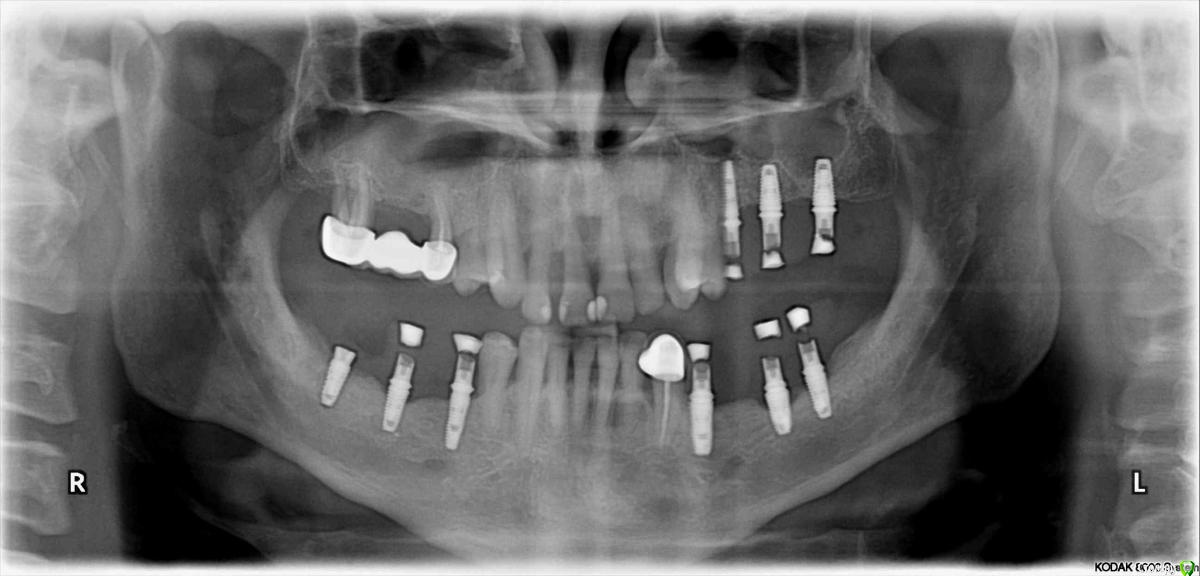

Я тут недавно удивлялся работе @AlexanderGudkov с "неправильным" протезированием и правильными результатами, сегодня показываю свой собственный "необъяснимый" опыт

Я вот, в общем то, о том же. Но почему за 4 года в этом случае все стало только лучше? Что-то в моей философии о БШ, значит, неверно

У Вас получилось «не благодаря ,а вопреки». На каком то этапе наросла кость на плечо импланта и все живет . Обычно получается как r_b показал(кошмар! Такую работу запороли). В общем,на авось прокатит надеяться не надо,лучше не давать повода и контролировать каждый этап. И беречь десну,будет прикреплённая десна-будет и кость-будет жив имплант.

Я долгое время считал разделение платформ и/или соблюдение БШ ключевыми факторами для стабильности периимплантных тканей (при адекватной нагрузке по умолчанию). А это, видимо, не так.